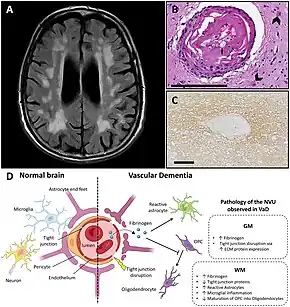

Pathology

Gross examination of the brain may reveal noticeable lesions and damage to blood vessels. Accumulation of various substances such as lipid deposits and clotted blood appear on microscopic views. The white matter is most affected, with noticeable atrophy (tissue loss), in addition to calcification of the arteries. Microinfarcts may also be present in the gray matter (cerebral cortex), sometimes in large numbers. Although atheroma of the major cerebral arteries is typical in vascular dementia, smaller vessels and arterioles are mainly affected.